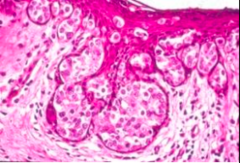

Comedo type

-subtype of DCIS -shows necrosis -high grade 3 -solid or comedo growth patterns -high grade ductal carcinoma in situ, if there is a corresponding variation in nuclei or evidence of necrosis.